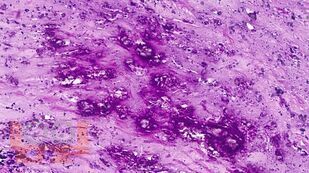

В учебном пособии представлен теоретический материал, перечень макропрепаратов и микропрепаратов, демонстрирующих типовые проявления патологических процессов. В цветных иллюстрациях и в описании микропрепаратов сделан акцент на наиболее важных гистологических изменениях, позволяющих на светооптическом уровне диагностировать и дифференцировать состояния, отклоняющиеся от нормы, в том числе с использованием различных гистологических окрасок. Пособие помогает выделить главные аспекты изучаемых патологических процессов, организовать и конкретизировать учебный процесс.